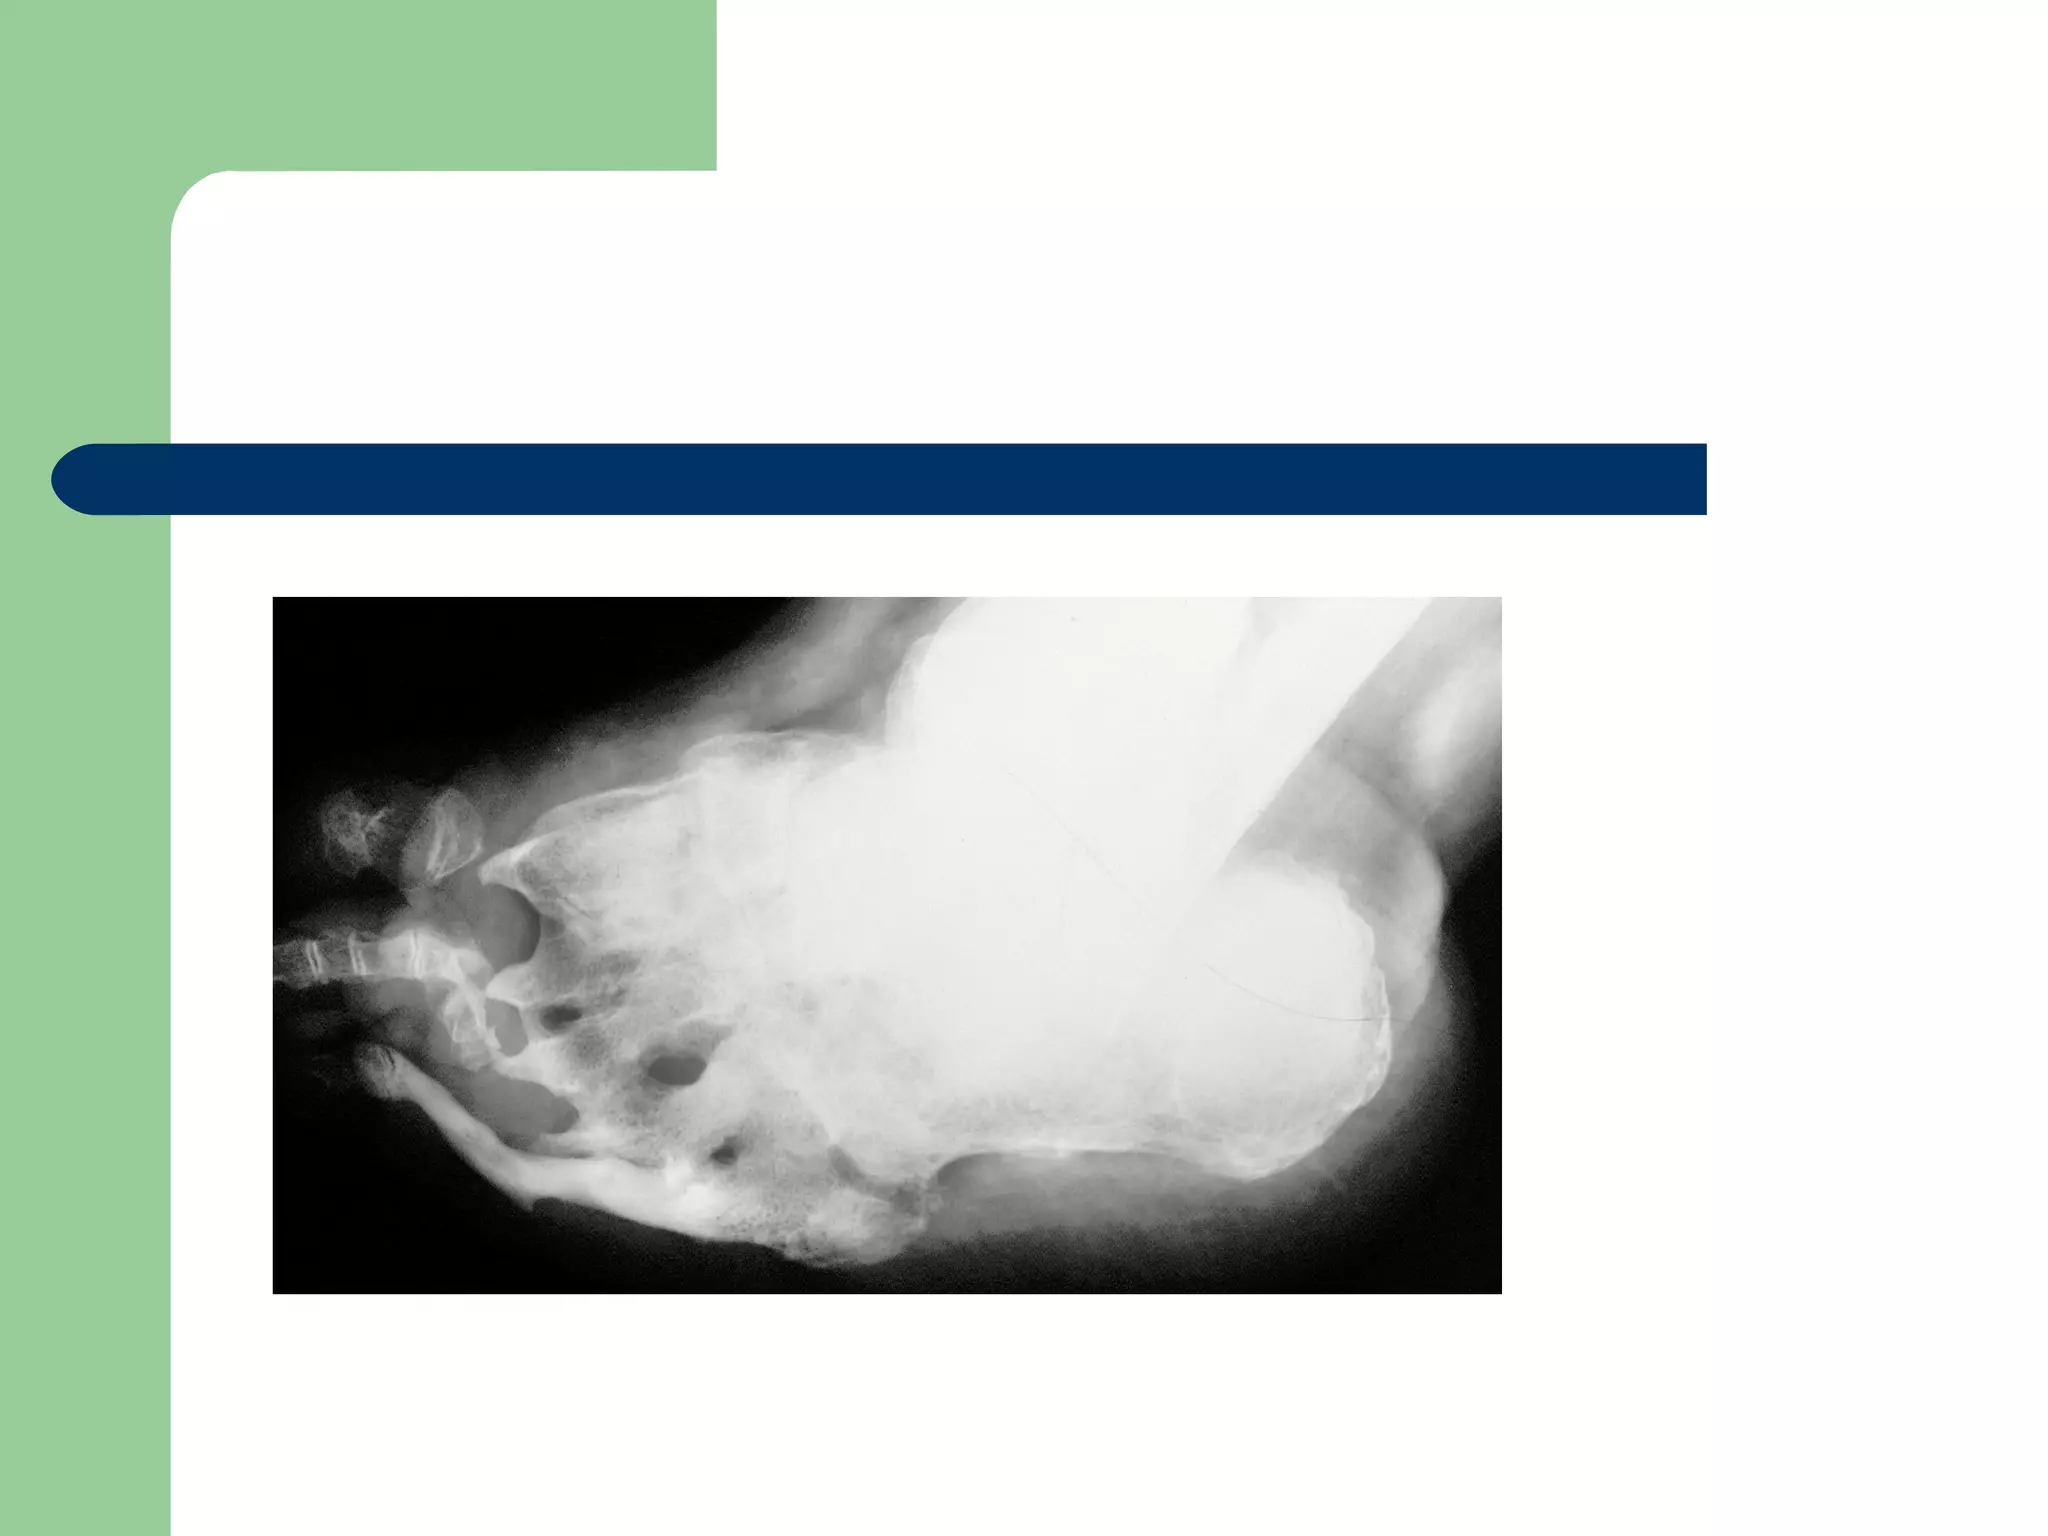

 With the Lisfranc pattern, breakdown initially occurs along the medial column,

with late changes progressing to the lateral column. The arch abducts and

prominences develop, leading to deformity, fullness, and ulceration. The

naviculocuneiform pattern leads to collapse at the naviculocuneiform joint, with

development of a lateral rocker-bottom deformity. The perinavicular pattern is

caused by osteonecrosis or fracture of the navicular. The lateral arch height

decreases, leading to a lateral rocker and shortening of the medial column.

Eventually this breakdown progresses to the central aspect of the foot, with

severe plantar flexion of the talus and eventual ulceration. The transverse tarsal

pattern is caused by lateral subluxation of the navicular on the talus and

abduction of the foot with a valgus calcaneus. Calcaneal pitch eventually

decreases, and a central rocker develops at the calcaneocuboid joint. In late

stages, the talus is completely dislocated from the navicular, and ulceration

develops at the calcaneocuboid interval. All four patterns eventually progress to

a rocker-bottom deformity and chronic ulceration.